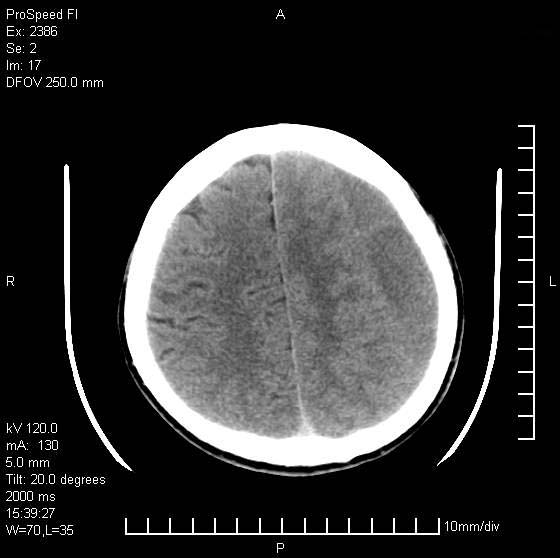

以下是引用天南地北在2007-9-19 18:43:00的发言:[br]典型慢性硬膜外血肿[br][br][本贴已被 天南地北 于 2007-9-19 18:44:11 修改过]

以下是引用曼一拍在2007-9-20 11:06:00的发言:[br]支持慢性硬膜下血肿.[br]慢性硬膜下积液:血肿有包膜,ct值稍高于脑脊液,增强可有染色。不典型者血肿可多呈梭形.是硬脑膜与蛛网膜之间的潜在腔隙内的血肿。[br]鉴别:[br]1\\硬膜外血肿:是颅脑外伤后脑膜或板障内血管破裂,血液在颅骨与硬膜之间积聚所致.通常是脑膜动脉破裂,也可因静脉窦破裂或颅骨的板障静脉出血,发生于外伤的着力部,常与颅骨骨折并存。脑膜动脉出血则急,若是板障静脉出血在则可有慢性。[br]2\\硬膜下积液:(硬膜下水瘤)[br]是由于蛛网膜破裂,脑脊液经蛛网膜破口进入硬膜下腔不能回流。或水肿阻塞而形成。[br]ct表现:颅骨内板下方新月形低密度区近似脑脊液密度;占位效应清,周围无脑水肿。[br]